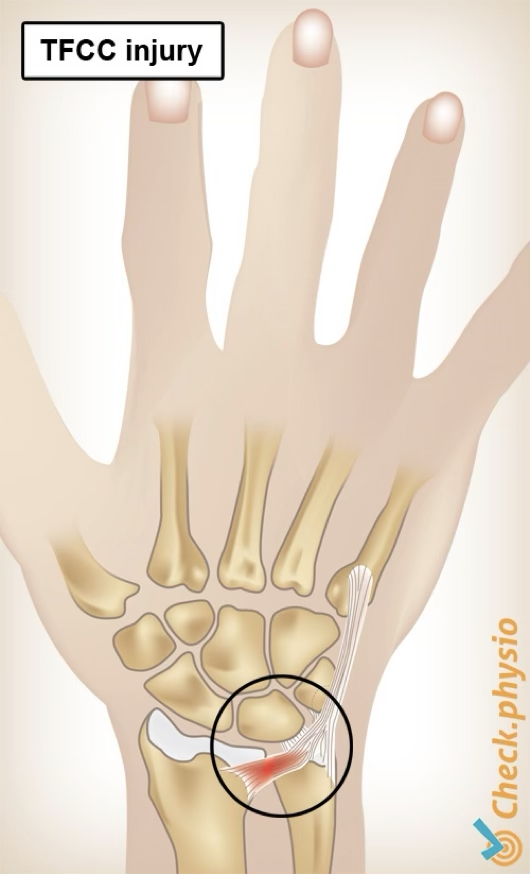

TFCC injury

TFCC is injured when patient has a violent twist of the wrist, typically with a hyperextension

symptoms: pain on ulnar side, possible clicking, lack of wrist extension, swelling

treatment: if suspected, send for imaging

may need splint for about 4 weeks (rest), then start with strengthening and ROM exercises, bad case may need surgery

Triangular fibrocartilage complex (TFCC)

combination of ligaments and “meniscus” cartilage on ulnar side